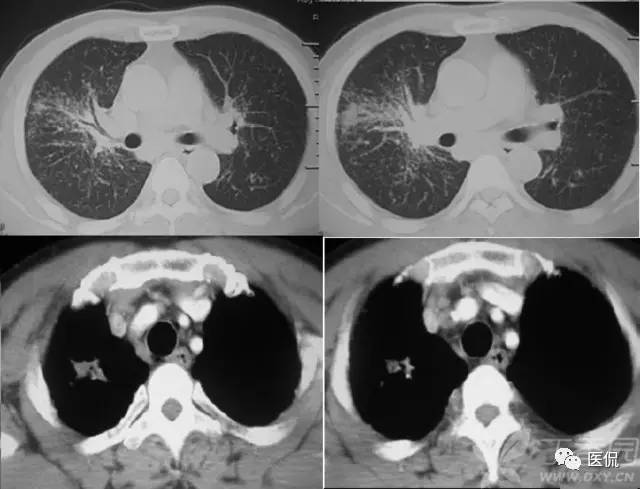

胸腹水鉴别四联症

1、膈肌征:横隔顶向头侧凸出,低密度影在膈外周为胸水,在膈内为腹水。

2、膈脚移位征:胸水时压迫膈脚向前、向外侧移位。

3、界面征:肝与肺在层面上的分界一般是清晰的,腹水时也清晰明确,而当胸水时则肝肺分界不清晰。

4、肝裸区征:肝的背侧内部肝与膈肌直接相贴,此为裸区,产生腹水时液体不在此区潴留。